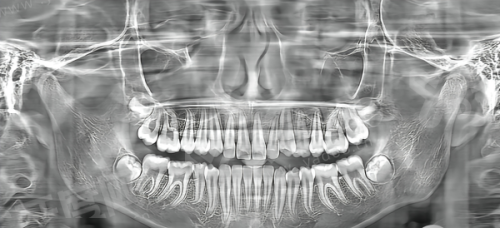

1、传统种牙往往依赖医生手感,而这里采用 CBCT 三维影像扫描结合口内扫描数据,术前就能在电脑上模拟出种植体植入的角度、深度和位置,误差控制在微米级别。

2、通过制作个性化手术导板,医生在操作时只需沿着导板通道进行,避免了切开翻瓣的大创伤,特别适合高龄老人或患有轻微基础病的缺牙患者,术后肿胀轻。

3、这种技术不仅缩短了手术时间,还能有效避开神经管和上颌窦等重要解剖结构,让单颗缺失或多颗连续缺失的患者都能获得更稳定的初期固位力。